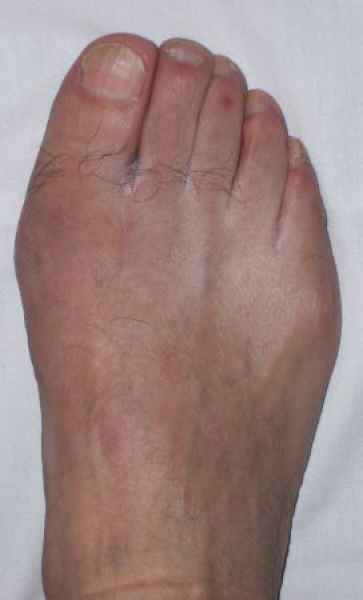

La marcha no solo es característica de la especie humana sino también de cada persona, y más aún varía según el estado de ánimo del momento. Una patología en los pies, se traduce en el rostro, en el ánimo, en el psiquismo. No sólo el dolor produce estos efectos, también un pie deformado o poco estético. En nuestra sociedad, la estética constituye un valor muy apreciado y estas alteraciones causan vergüenza fundamentalmente en las mujeres, que esconden en la playa sus pies en la arena y no pueden usar calzados elegantes.

Tanto la estructura del pie como su funcionalismo que es la marcha, pueden ser asiento y manifestación respectivamente de alteraciones locales ó sistémicas, por lo que su cuidadoso examen resulta de extrema utilidad diagnóstica.